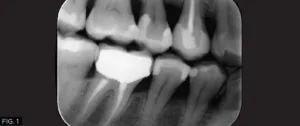

A young female physician presented to my office with a chief complaint of sensitivity to cold and sweets in her lower right dentition which has been persistent for approximately 1 month. Upon clinical and radiographic examination, it was determined that her lower right first premolar #28 (#44) had a previous restoration that had fractured and was compromised by recurrent caries. (FIG. 1)

The carious lesion was rather deep into the tooth according to the radiographic image but not wide. The carious lesion was less than ½ the distance between the buccal/lingual cusp distance making this an excellent case for a direct composite restoration. (FIG. 2)